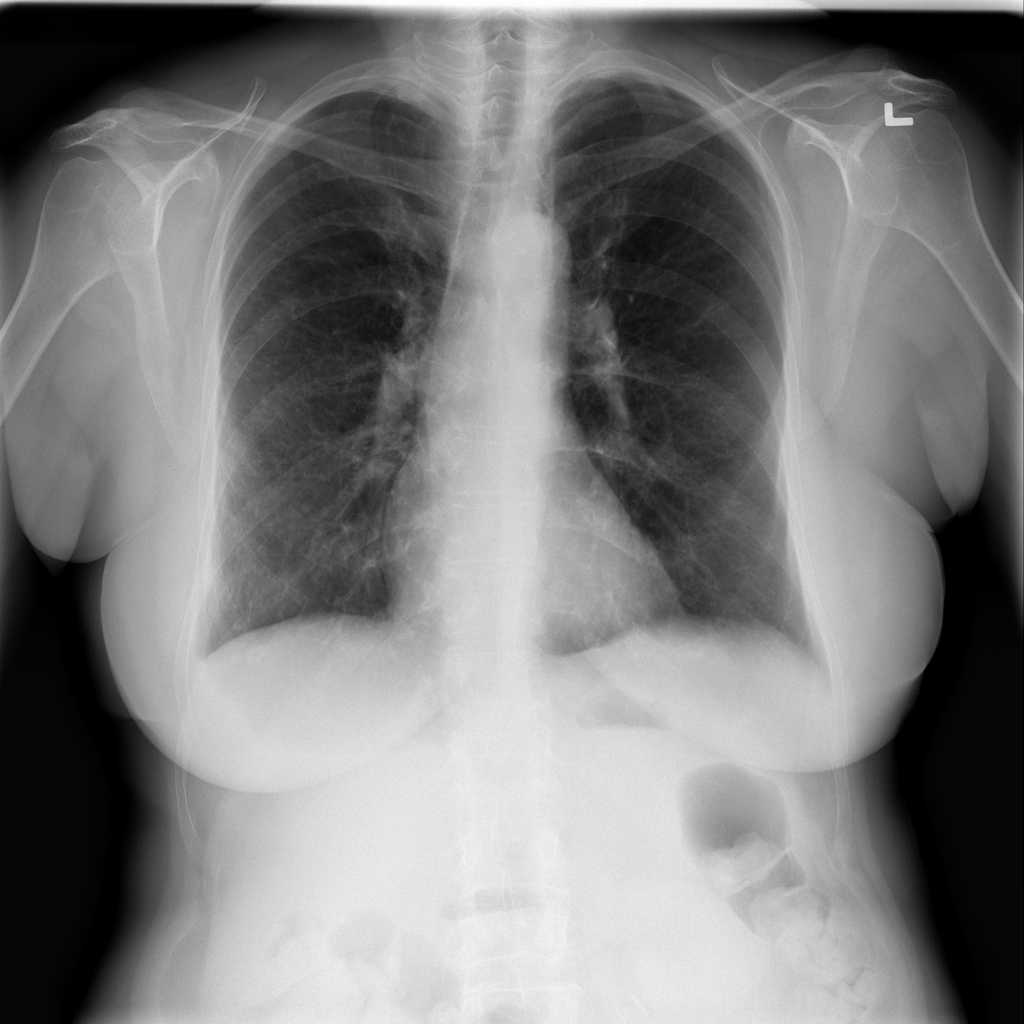

PAT-E960 · IMG-002Fibrosis

PAT-E960 · IMG-002

PA